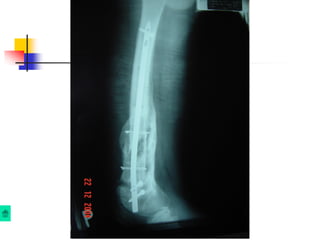

Baát ñoäng xöông

Coá ñònh ngoaøi:

 Coáñònhngoaøilaøphöôngphaùptieâuchuaåntrongvieâmxöông

khôùpgiaû.

- Theo ñuùng nguyeân taéc coá ñònh ngoaøi

- Giöõ trong moät thôøi gian daøi, coù theå moät naêm hoaëc hôn.

- Thayñinh neáu bònhieãm truøng chaânñinh

- Hai loaïi CÑN löïachoïn laø Ilizarov vaø khung ñôn giaûnduøng ñinh Chanz .

Ñinh, neïp:

 Nguy cô nhieãm truøng cao, nhöng moät soá

tröôøng hôïp cuõng duøng.